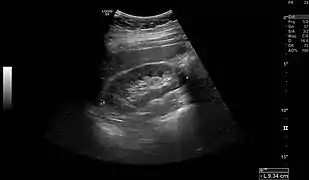

Imaging

Renal ultrasonography is essential in the diagnosis and management of kidney-related diseases.[44] Other modalities, such as CT and MRI, should always be considered as supplementary imaging modalities in the assessment of renal disease.[44]